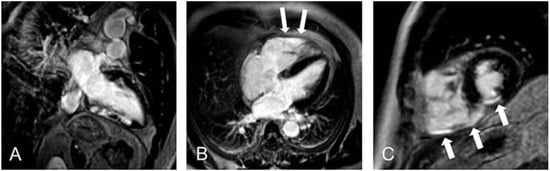

Figure 3. Late-gadolinium-enhancement-Aufnahmen eines Patienten nach Hinterwandinfarkt. (A) 2-Kammer-Blick (B) 4-Kammer-Blick (C) Kurzachsenorientierung LV/RV. Deutlich zu sehen ist die Beteiligung des rechtsventrikulären Myokards (B,C).

Viables Myokard und Narbengewebe